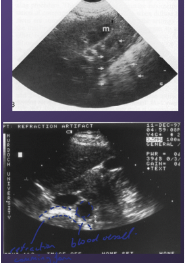

Name this type of artefact and state the cause of it:

Comets tail. This is caused by an irregular tissue surface that could include pleura, bowel gas, gas bubbles and metallic objects.

Name the artefact below and provide an example of where this type of artefact would be observed.

This is a refraction - edge shadowing artefact. This would be caused by kidney, renal medulla, gall bladder and blood vessels.